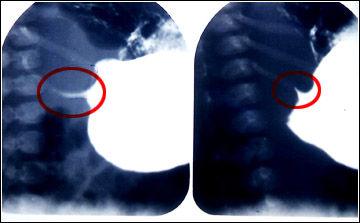

Hipertrofia de la musculatura pilórica que dificulta el vaciamiento gástrico. Las radiografías con medio de contraste muestran la estrechez del canal pilórico (círculo rojo).